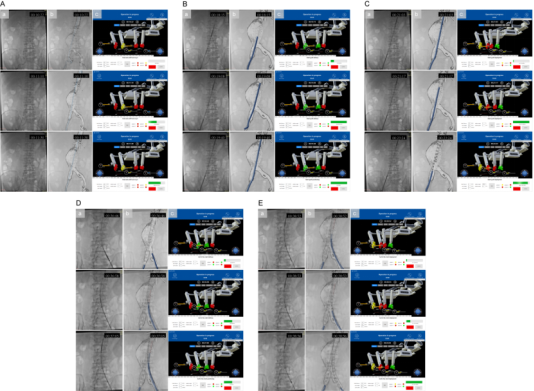

作為國家“新一代人工智能”專項(xiàng)承擔(dān)單位,奧朋醫(yī)療憑借近百項(xiàng)國內(nèi)外核心專利技術(shù)儲備,此次手術(shù)實(shí)現(xiàn)四大核心突破,樹立行業(yè)新標(biāo)桿: 01 全球首創(chuàng) EVAR 全流程自動(dòng)化 首次實(shí)現(xiàn)從導(dǎo)絲推進(jìn)、導(dǎo)管輸送到支架精準(zhǔn)釋放的全環(huán)節(jié)無人干預(yù)操作,徹底突破現(xiàn)有機(jī)器人“手控為主、半自動(dòng)為輔”的技術(shù)局限,將血管介入手術(shù)的自動(dòng)化程度提升至全新高度。 02 獨(dú)創(chuàng)“手術(shù)步驟參數(shù)化”新范式: 基于奧朋醫(yī)療自主研發(fā)的 Endosize軟件,通過術(shù)前 CTA影像3D重建與精準(zhǔn)建模,將復(fù)雜EVAR手術(shù)拆解為可編程、可重復(fù)的標(biāo)準(zhǔn)單元,自動(dòng)生成器械運(yùn)動(dòng)參數(shù),推動(dòng)血管介入治療從“經(jīng)驗(yàn)依賴”向“標(biāo)準(zhǔn)量化”轉(zhuǎn)型。 03 高兼容+多重安全保障體系: 系統(tǒng)兼容市售主流導(dǎo)絲、導(dǎo)管及支架等常規(guī)耗材,解決了傳統(tǒng)機(jī)器人“耗材適配性差”的行業(yè)痛點(diǎn);內(nèi)置2N力反饋閾值自動(dòng)暫停機(jī)制,搭配人機(jī)協(xié)同檢查點(diǎn)、物理+虛擬雙急停按鈕,實(shí)現(xiàn)“精準(zhǔn)操作+安全可控”的雙重保障。 04 構(gòu)建開放式智能介入平臺: 該平臺依托奧朋醫(yī)療“血管介入領(lǐng)域達(dá)芬奇”的技術(shù)定位,可無縫拓展至冠脈、神經(jīng)、外周等8大介入領(lǐng)域,為未來融合AI自主導(dǎo)航、5G遠(yuǎn)程手術(shù)奠定堅(jiān)實(shí)基礎(chǔ),彰顯強(qiáng)大技術(shù)延展性。 圖示:基于3D打印血管模型的體外驗(yàn)證實(shí)驗(yàn)。圖中展示了支架植入的關(guān)鍵步驟,包括主體支架輸送、精確定位、釋放以及分支支架植入。本圖包含三個(gè)視角:(A) 聚焦于血管模型的近景視圖;(B) 展示整個(gè)實(shí)驗(yàn)環(huán)境的廣角視圖;(C) 操作臺監(jiān)視器界面的截圖。 圖示:自動(dòng)化機(jī)器人輔助EVAR人體驗(yàn)證的支架植入過程。在導(dǎo)入超硬導(dǎo)絲后(見圖4A),首先以10 mm/s的速度快速將支架輸送系統(tǒng)推進(jìn)至目標(biāo)位置附近,隨后以1 mm/s的慢速進(jìn)行微調(diào),最終實(shí)現(xiàn)支架在目標(biāo)點(diǎn)的精準(zhǔn)定位(見圖4B)。隨后進(jìn)行支架釋放,并通過逆時(shí)針旋轉(zhuǎn)釋放手柄5400°(轉(zhuǎn)速90°/s)完成裸段釋放過程(見圖4C)。在人工完成對側(cè)短腿超選并建立超硬導(dǎo)絲通道后,分支支架以與主體支架相同的方式輸送并釋放(見圖4D、E)。 破解行業(yè)痛點(diǎn),奧朋醫(yī)療給出中國方案 血管介入手術(shù)機(jī)器人雖已在臨床展現(xiàn)出“提升精度、減少輻射”的顯著優(yōu)勢,但長期面臨兩大瓶頸:一是難以兼容常規(guī)耗材,無法滿足EVAR等復(fù)雜多器械協(xié)同手術(shù)需求;二是自動(dòng)化局限于單一步驟,難以實(shí)現(xiàn)全流程閉環(huán)操作。而腹主動(dòng)脈瘤作為“人體定時(shí)炸彈”,其主流治療方式EVAR手術(shù)對操作精度、流程連貫性要求極高,傳統(tǒng)人工手術(shù)不僅術(shù)者面臨高輻射風(fēng)險(xiǎn),還存在因經(jīng)驗(yàn)差異導(dǎo)致的診療同質(zhì)化難題。 在此背景下,奧朋醫(yī)療深耕“醫(yī)工融合”創(chuàng)新理念,針對性研發(fā)全自動(dòng)、高兼容、安全可控的主從式血管介入手術(shù)機(jī)器人平臺,精準(zhǔn)破解行業(yè)痛點(diǎn),為復(fù)雜血管介入手術(shù)提供了兼具臨床適配性與技術(shù)先進(jìn)性的中國解決方案。 硬核技術(shù)支撐,臨床數(shù)據(jù)彰顯實(shí)力 該平臺依托奧朋醫(yī)療“血管介入領(lǐng)域達(dá)芬奇”的技術(shù)定位,可無縫拓展至冠脈、神經(jīng)、外周等8大介入領(lǐng)域,為未來融合AI自主導(dǎo)航、5G遠(yuǎn)程手術(shù)奠定堅(jiān)實(shí)基礎(chǔ),彰顯強(qiáng)大技術(shù)延展性。 本次研究采用奧朋醫(yī)療自主研發(fā)的主從式機(jī)器人平臺,集成多自由度機(jī)械臂與高精度驅(qū)動(dòng)模塊,通過“術(shù)前精準(zhǔn)規(guī)劃—術(shù)中自動(dòng)執(zhí)行—階段協(xié)同確認(rèn)”的閉環(huán)流程,實(shí)現(xiàn)毫米級操作精度。研究先經(jīng)3D打印血管模型充分驗(yàn)證,再成功應(yīng)用于4例腎下型腹主動(dòng)脈瘤患者,取得卓越臨床成果: ? 手術(shù)成功率100%:4例患者均順利完成全流程自動(dòng)化手術(shù),術(shù)后CTA證實(shí)支架定位精準(zhǔn),無內(nèi)漏及相關(guān)并發(fā)癥; ? 診療效率大幅提升:平均手術(shù)時(shí)間僅110分鐘,透視時(shí)間19分鐘,較傳統(tǒng)手術(shù)顯著縮短; ? 輻射防護(hù)成效顯著:術(shù)者輻射劑量低至4mGy,較傳統(tǒng)手術(shù)減少90%以上,從根本上保障醫(yī)護(hù)人員職業(yè)健康; ? 穩(wěn)定性全面驗(yàn)證:所有自動(dòng)化步驟均未發(fā)生意外中斷,無需人工接管,充分證明系統(tǒng)的臨床可靠性。 (圖示:血管介入手術(shù)機(jī)器人的組成與工作原理。(A) 血管介入手術(shù)機(jī)器人整體示意圖。手術(shù)過程中,術(shù)者坐于操作臺前(位于鉛屏后方),遠(yuǎn)程控制從端機(jī)械單元;(B) 操作臺的顯示界面與功能說明;(C) 自動(dòng)化機(jī)器人輔助EVAR手術(shù)的執(zhí)行流程圖。) (圖示:基于Endosize軟件的EVAR術(shù)前規(guī)劃。圖中展示了中心線及關(guān)鍵定位點(diǎn)。導(dǎo)絲的移動(dòng)距離為從Pl點(diǎn)至P1點(diǎn);導(dǎo)管的移動(dòng)距離為從Pr點(diǎn)至P2點(diǎn);主體支架的移動(dòng)距離為從Pr點(diǎn)至P3a點(diǎn);分支支架的移動(dòng)距離為從Pl點(diǎn)至P4a點(diǎn)。) 引領(lǐng)行業(yè)變革,繪就智能介入新藍(lán)圖 作為當(dāng)前全球唯一實(shí)現(xiàn)冠脈、外周、主動(dòng)脈介入手術(shù)同步臨床推進(jìn)的企業(yè),奧朋醫(yī)療此次突破性成果,不僅驗(yàn)證了全自動(dòng)化EVAR手術(shù)的臨床可行性,更通過標(biāo)準(zhǔn)化范式構(gòu)建,為縮小不同層級醫(yī)療機(jī)構(gòu)技術(shù)差距、提升基層診療同質(zhì)化水平提供了有效路徑。 未來,奧朋醫(yī)療將持續(xù)深化“精準(zhǔn)、智能、微創(chuàng)”的技術(shù)理念,進(jìn)一步拓展該平臺至復(fù)雜主動(dòng)脈病變、神經(jīng)血管介入等更多場景,并融合AI實(shí)時(shí)導(dǎo)航、5G遠(yuǎn)程手術(shù)等前沿技術(shù),推動(dòng)血管介入手術(shù)向“自主決策、全域覆蓋、優(yōu)質(zhì)資源下沉”的更高階段邁進(jìn)。正如奧朋醫(yī)療的發(fā)展愿景——致力于成為“血管介入領(lǐng)域的達(dá)芬奇”,以中國智造打破國際技術(shù)壟斷,為全球患者帶來更安全、更高效、更可及的醫(yī)療服務(wù)。